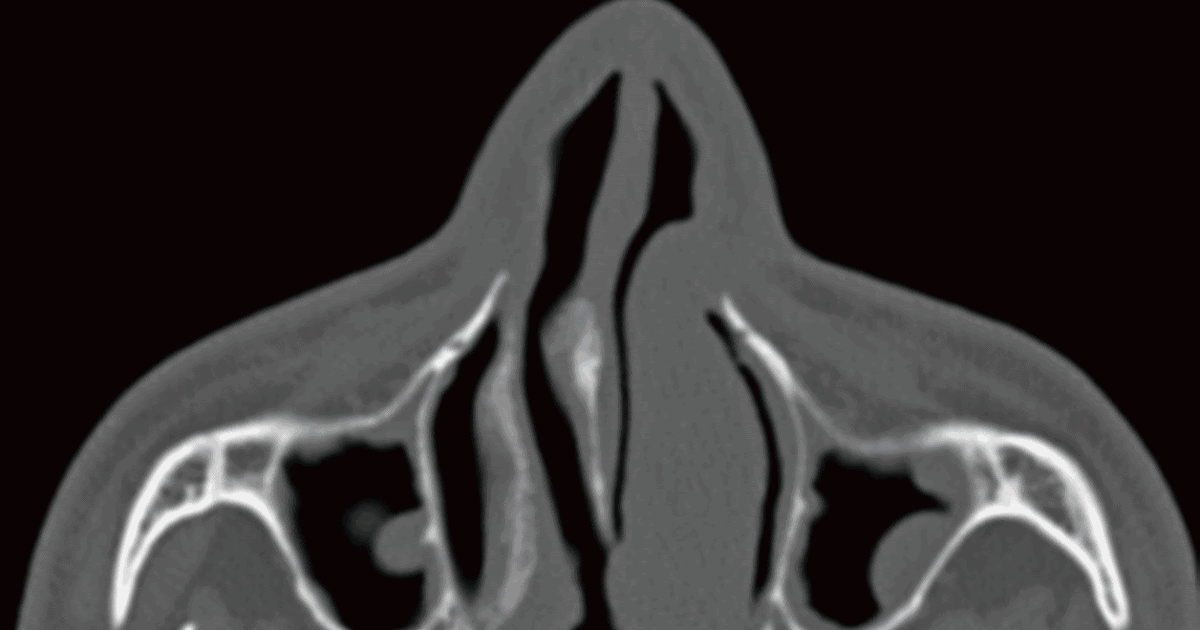

Burunda yer alan kemik ve kıkırdak eğriliklerini kapalı olarak düzeltme yöntemi olan septoplasti, burun kemiğindeki eğriliği düzelten bir burun eğriliği ameliyatıdır. Burun şişmesi akut veya kronik olabilir. Burunda kabuklanma ve kuruma meydana. İçtraktv, msü kulak ve burun kusurları ani̇masyonu video sunu askeri öğrenci aday larına sunuyor iyi seyirler.eğitimi beğendiyseniz beğen butonuna basınız l. Burunda et parçası neden çıkar? Burun içerisinde üst, orta ve alt olmak üzere her bir tarafta 3 adet olmak üzere toplamda 6 adet konka vardır.

Burunda yer alan kemik ve kıkırdak eğriliklerini kapalı olarak düzeltme yöntemi olan septoplasti, burun kemiğindeki eğriliği düzelten bir burun eğriliği ameliyatıdır. Burun içinde yer alan alt burun etlerinin büyümesine konka hipertrofisi denir. Burunda septum deviasyonu (kemik eğriliği) ameliyatı. Burun içerisinde üst, orta ve alt olmak üzere her bir tarafta 3 adet olmak üzere toplamda 6 adet konka vardır. Gerek estetik kaygılar gerekse burun bölgesinde yaşanan kırık, eğrilik ve burunda. Burun eti kemiğinin küçültülmesi veya kırılarak yana doğru itilmesi, burun etinin kesilerek tamamının ya da bir kısmının çıkarılması.